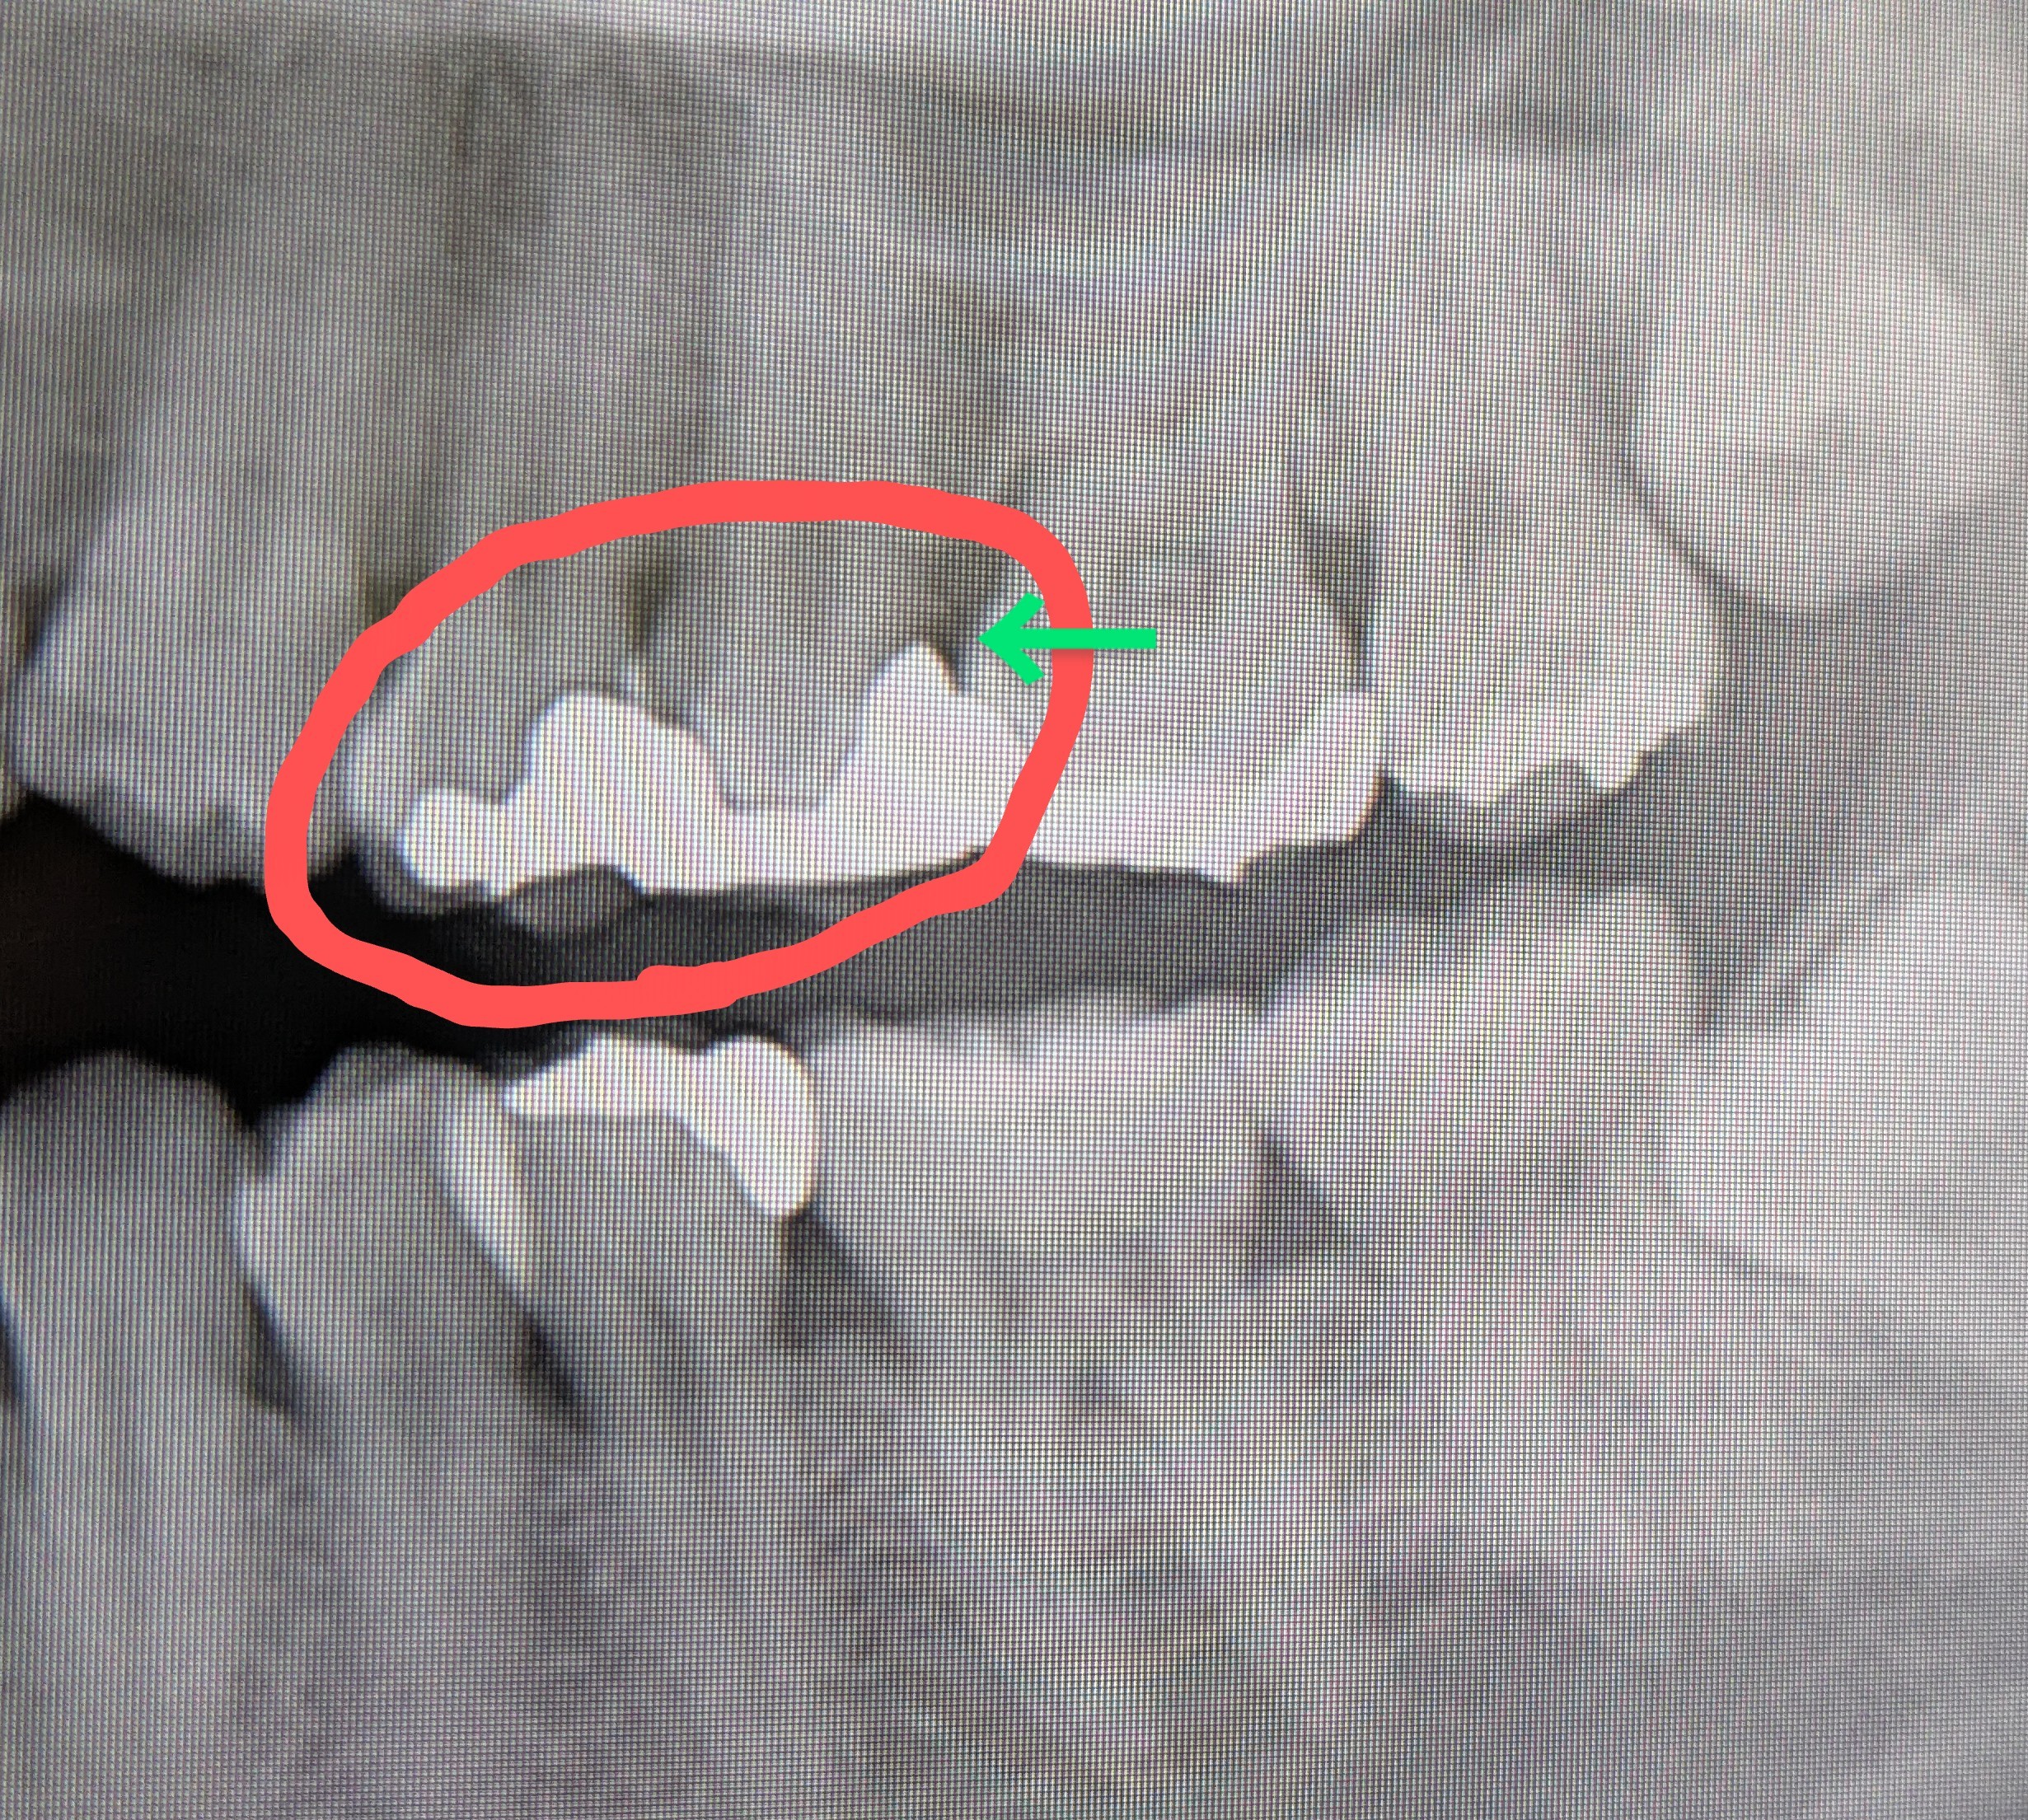

銀歯の奥に膿があり抜歯と言われました。抜歯以外の治療方法はありませんか?

回答数:2